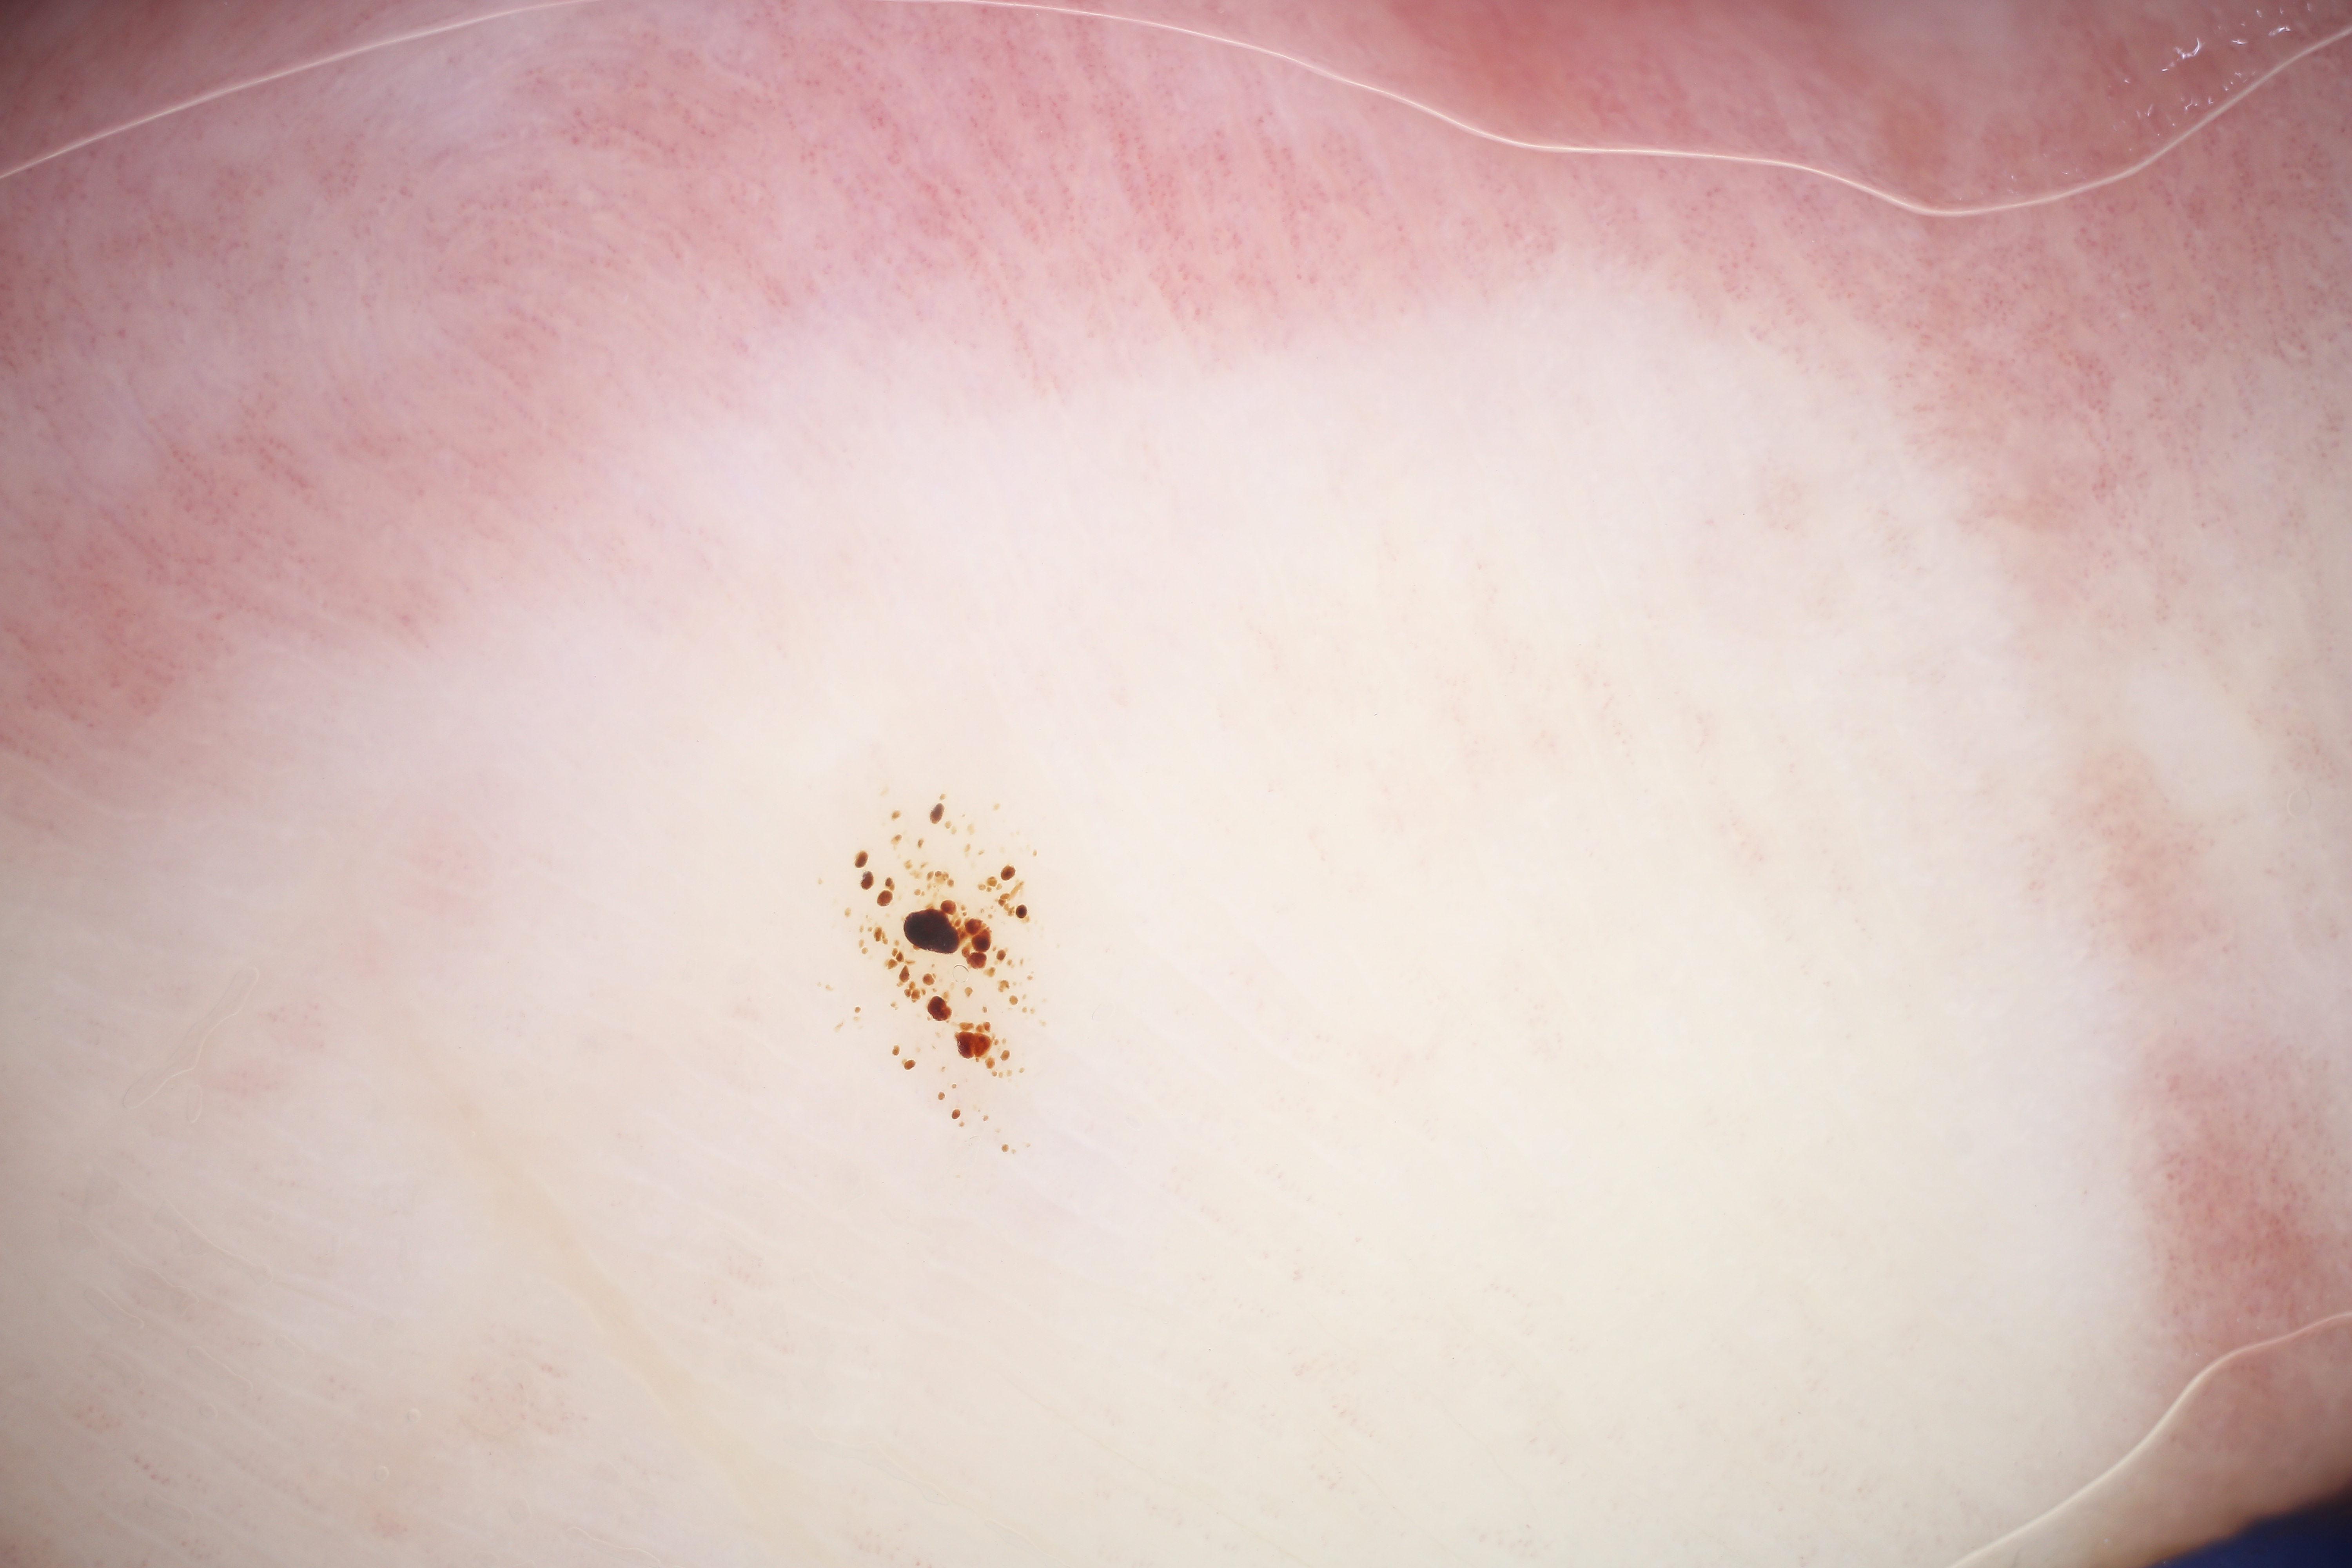

{

"acquisition_day": 428,

"age_approx": 75,

"anatom_site_general": "head/neck",

"concomitant_biopsy": true,

"diagnosis_1": "Malignant",

"diagnosis_2": "Malignant melanocytic proliferations (Melanoma)",

"diagnosis_3": "Melanoma Invasive",

"diagnosis_confirm_type": "histopathology",

"image_manipulation": "instrument only",

"image_type": "dermoscopic",

"lesion_id": "IL_2975036",

"melanocytic": true,

"patient_id": "IP_1039004",

"sex": "female"

}